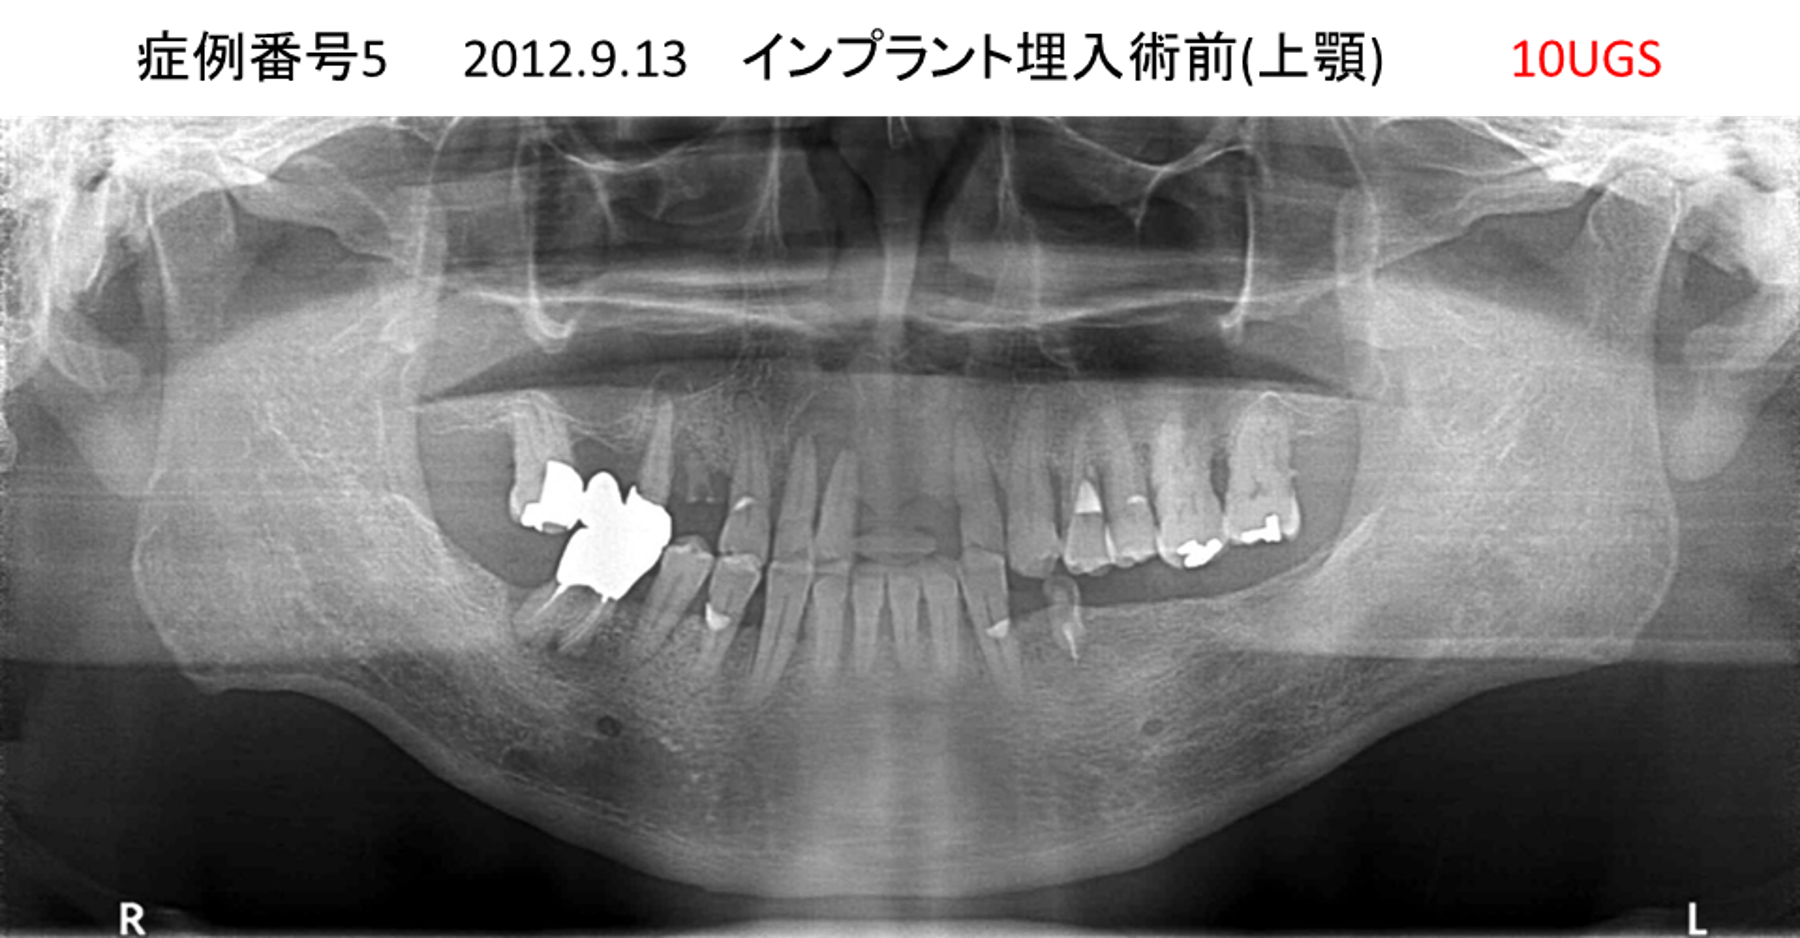

ご飯を美味しく食べたい/人前で笑えるようになりたい患者様のインプラント症例

| 治療名称 |

インプラント |

| 治療費用 |

480万円+税 |

| 治療期間 |

6か月 |

| 患者さんの症状(主訴) |

おいしいご飯が食べられるようになりたい 人前で笑えるようになりたい |

| 治療内容 |

サイナスリフト 抜歯即時インプラント |

| 治療結果 |

何でも食べられるようになった 人前で大口を開けて笑えるようになった |

| 治療の注意点(リスク/副作用) |

インプラントが壊れた場合は再治療が必要 |